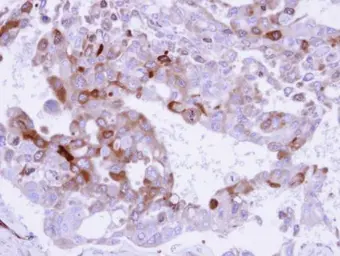

Anti-Glutamine synthetase antibody used in IHC (Paraffin sections) (IHC-P). GTX109121

GTX109121 IHC-P Image

Immunohistochemical analysis of paraffin-embedded H441 xenograft , using Glutamine Synthetase (GTX109121) antibody at 1:500 dilution.

Antigen Retrieval: Trilogy™ (EDTA based, pH 8.0) buffer, 15min